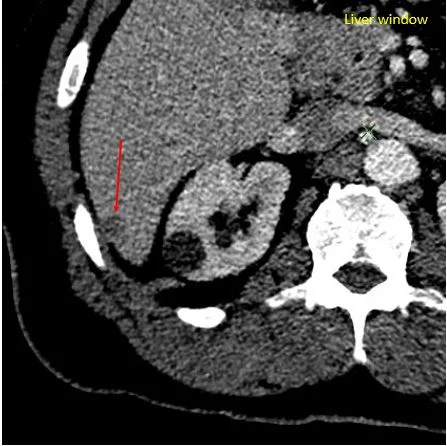

Liver windows make the lesion more conspicuous.